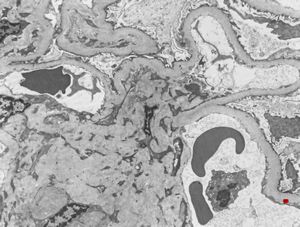

membranoproliferative glomerulonephritis

M,37y. | type I membranoproliferative glomerulonephritis (mesangiocapillary)